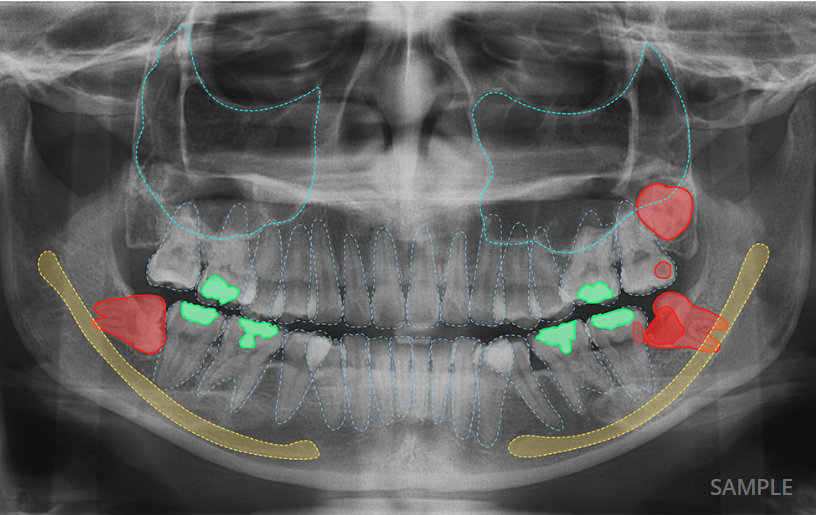

AI X-ray Detection & Automated Dental Charting

Ever wonder what your dental x-ray really shows? With our AI technology, you can now see it more clearly than ever.

The AI analyses your x-ray images within seconds and highlights areas that may need attention, such as tooth decay, impacted tooth, bone loss and etc. These are shown directly on your x-ray image, helping you understand what is going on at a glance.

The system also automatically updates your dental chart, which is part of your dental records, saving time and ensuring every detail is properly recorded.

• Clear, colour-marked visualisation on your x-ray